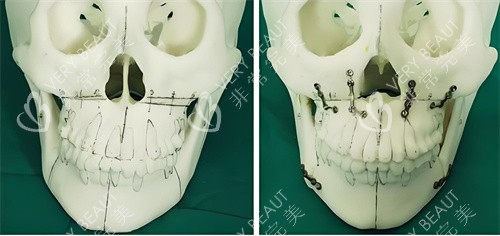

3D导板技术发明人:自主研发的“普式导板正颌术”将截骨误差控制在0.1毫米以内,这项技术已被纳入国境内颌面外科医师培训教材。

智能化术前设计:通过CT扫描获取患者颌面数据,运用3D智能系统重建三维模型,提前模拟术后结果。

术中“零误差”操作:定制的3D截骨导板可精密定位截骨线,避免损伤神经和血管。

复杂颅颌面修复:一位因瘤切除导致面部塌陷的患者,何锦泉通过自体骨移植+3D导板定位,成功重建面部轮廓,术后外观与术前模拟结果几乎一致。